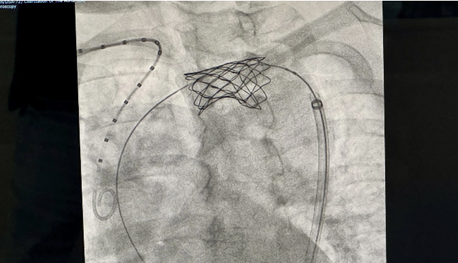

ដើម្បីព្យាបាលជំងឺស្ទះសរសៃឈាមបេះដូងអាទែអ្នកជំនាញប្រើវិធីសាស្រ្តអន្តរាគមន៍ដាក់ stent អាទែដោយសារតែមានសុវត្ថិភាព និងប្រសិទ្ធភាពរបស់វា។ ប៉ុន្តែនៅក្នុងករណីរបស់ អ្នកស្រី P.T.L. ការដាក់ stent គឺនៅកន្លែងបត់នៃសរសៃអាទែដែលកាន់តែពិសេស។ ជាមួយនឹងនីតិវិធីដាក់Stent ហើយអង្កត់ផ្ចិតនៃកន្លែងផ្លូវចូលគឺមានទំហំត្រឹមតែ ២ទៅ៣ មីលីម៉ែត្រ។ ក្នុងករណីនេះ វេជ្ជបណ្ឌិត ទ្វឹង ត្រូវពង្រីកអង្កត់ផ្ចិតនៃកន្លែងចូលដល់ ៥ទៅ៦ មីលីម៉ែត្រ ដោយមានការគាំទ្រពីឧបករណ៍បិទ ពិសេសដើម្បីការពារការហូរឈាមដែលមិនអាចគ្រប់គ្រងបាន។

ដោយសារតែ stent ត្រូវបានដាក់នៅក្នុងអាទែនោះ វាមានទំហំធំ ដូច្នេះផ្លូវចូលតាម សរសៃឈាមធំត្រូវតែជ្រើសរើសនៅភ្លៅ។

លោកវេជ្ជបណ្ឌិត ទ្វឹង បានពន្យល់ថា« Stent ធម្មតានឹងមានប៉េងប៉ោងមួយបត់ចូលគ្នា។ នៅពេលដែលវាទៅដល់ទីតាំងដែលត្រូវការ ប៉េងប៉ោងនឹងពង្រីក ហើយ stent នឹងគៀបចូលជញ្ជាំងសរសៃ។ ជាពិសេស stent ដែលប្រើសម្រាប់ បងស្រី L. មានប៉េងប៉ោងពីរ ប៉េងប៉ោងតូចត្រូវបានពង្រីកមុន បន្ទាប់មកដល់ប៉េងប៉ោងធំ។ ពេលនោះ stent ទើបគៀបចូលជញ្ជាំងសរសៃ»។

វិធីសាស្រ្តនេះតម្រូវឱ្យវេជ្ជបណ្ឌិតធ្វើប្រតិបត្តិការយ៉ាងម៉ត់ចត់ ជៀសវាងករណីរបួសដល់សរសៃឈាម បណ្តាលឱ្យដាច់រលាត់ នាំឱ្យហូរឈាមមិនអាចគ្រប់គ្រងបាន។ លើសពីនេះ stent ត្រូវតែដាក់ក្នុងទីតាំងច្បាស់លាស់តាមការគ្រោងទុក ប្រសិនបើខុស វាអាចបំលាស់ទីទៅឆ្ងាយ។

ថ្ងៃទី ២៦ ខែវិច្ឆិកា លោកបណ្ឌិត វេជ្ជបណ្ឌិត ហូមិញទ្វឹង បានអន្តរាគមន៍ដោយផ្ទាល់នូវការប៉េងប៉ោងពង្រីក និងដំណើរការដាក់ stent ដែលមានការគាំទ្រពីម៉ាស៊ីនស្កេនឌីជីថល(DSA)។ វិធីសាស្រ្តនេះបានជោគជ័យ ៦០នាទី ក្រោយមកអ្នកជំងឺដឹងខ្លួនធម្មតា។